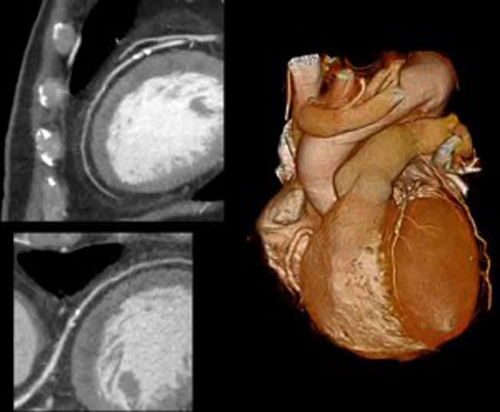

Per questo lo studio Cosmos è stato fatto senza un gruppo di controllo, esaminando alla Tac spirale tutti i soggetti arruolati (in totale 6.200 forti fumatori) e senza limitarsi a sole tre Tac, ma continuando a seguirli annualmente. Alla fine, all’Ieo sono state eseguite 40mila Tac che hanno portato a diagnosticare 297 carcinomi polmonari, nel 75% dei casi allo stadio iniziale (e dunque molto più facilmente curabili).

“Senza diagnosi precoce – ha spiegato a sua volta Massimo Bellomi, coordinatore insieme a Giulia Veronesi dello studio Cosmos – ancora oggi più del 70% dei tumori del polmone viene scoperto quando la malattia è già in fase avanzata, spesso inoperabile e con una percentuale di guarigione non superiore al 15%. La diagnosi precoce con Tac spirale ha ribaltato questa percentuale: più dell’80% dei pazienti può essere operato con un intervento conservativo, lobectomia invece che l’asportazione dell’intero polmone, e con una percentuale di sopravvivenza del 70% dopo 5-10 anni di controlli”.